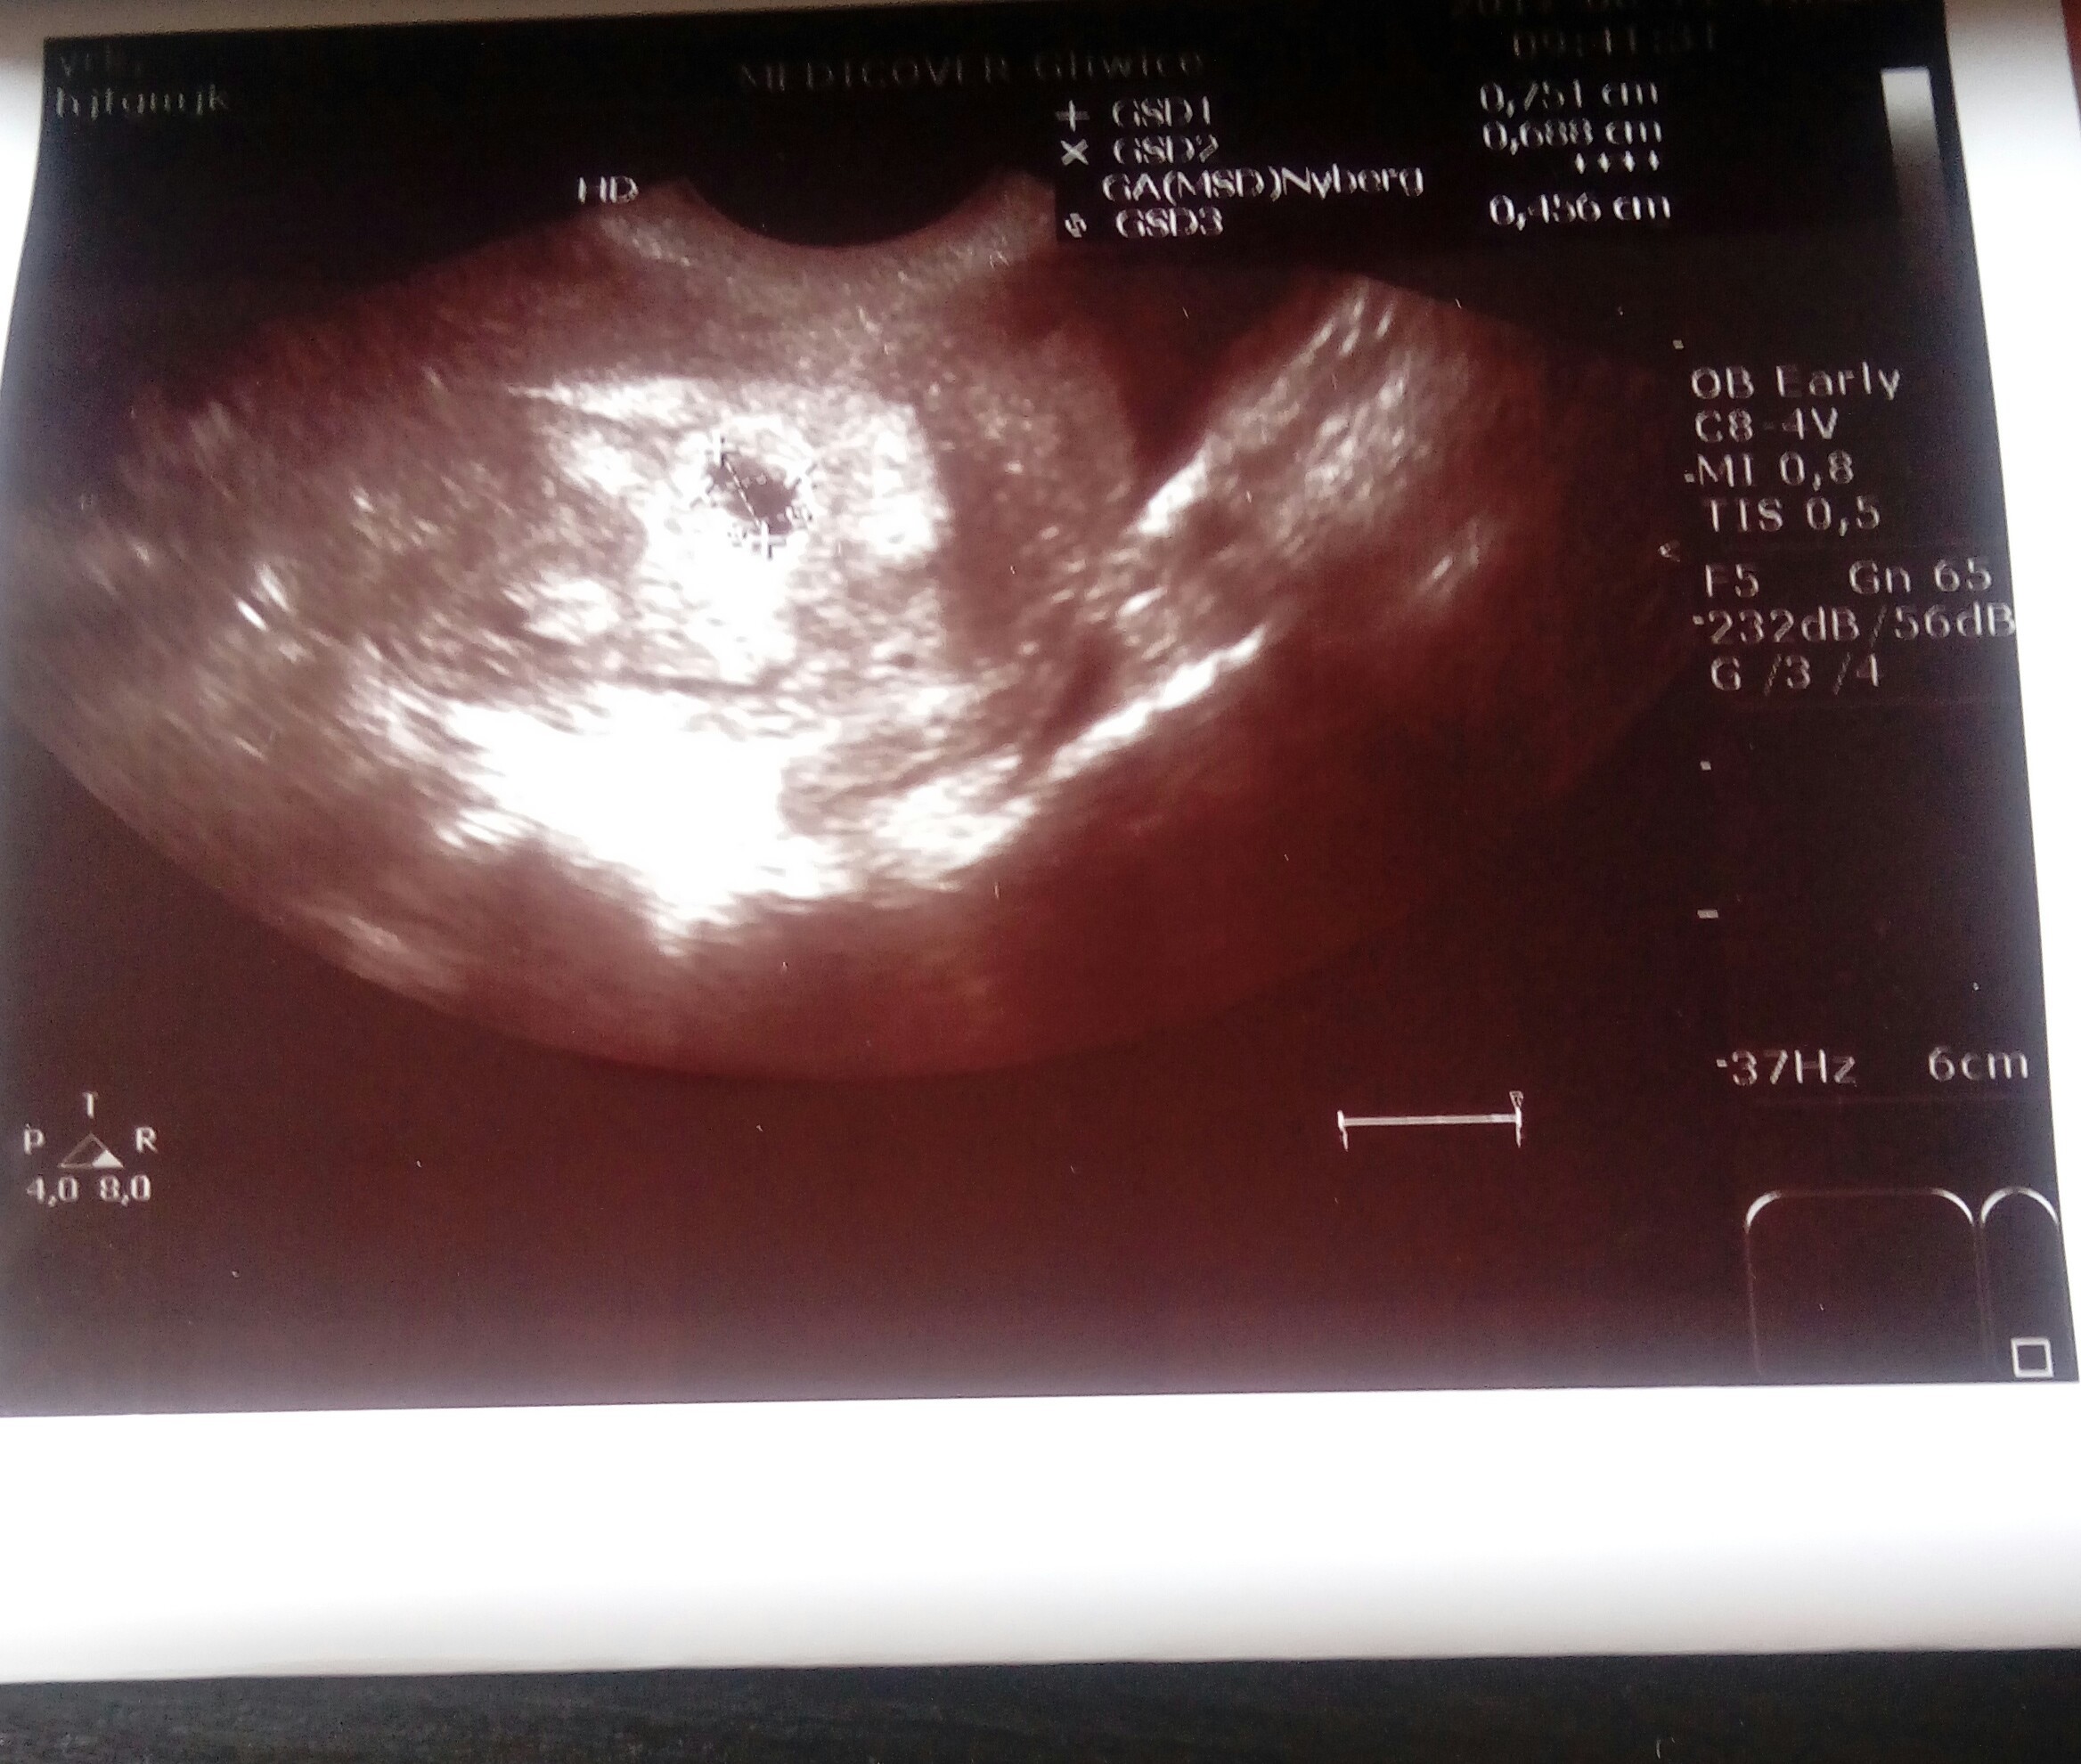

Witam wszystkie mamusie. Od kilku dni podczytuje forum i postanowilam tez dolaczyc choc jestem jeszcze pelna obaw. Obecnie jestem w 4t6d ciąży Ciąża wczoraj została potwierdzona przez usg na razie jest tylko mały pęcherzyk

Załączniki

• 20170812_144050-1.jpg

20170812_144050-1.jpg

658,6 KB · Wyświetleń: 109